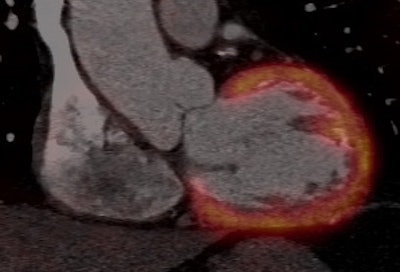

At the recent congress of the European Society of Cardiology (ESC), Dr. Aju Paul Pazhenkottil, a cardiac imaging specialist from Zurich University Hospital, demonstrated the predictive value of SPECT/CT for fusing myocardial perfusion imaging from SPECT with the complementary anatomical CT image.

For the study, 324 patients were divided into three types according to the results of the hybrid exam, a matched group with a finding of stenosis by coronary CT angiography (CTA) and a matching reversible SPECT defect, patients with unmatched coronary CTA and SPECT finding, and then patients found to be normal by both coronary CTA and SPECT.

Pazhenkottil told AuntMinnieEurope.com his group originally studied matched findings for PET and CT, though the assessment of ischemia by PET is not reimbursed in Switzerland. This preliminary work, "Integrated PET/CT for the assessment of coronary artery disease: a feasibility study," was published in the Journal of Nuclear Medicine in June 2005 (Vol. 46:6, pp. 930-935).